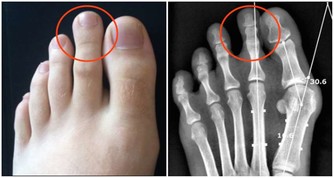

11、痛風、高尿酸血症

都是血液中尿酸過多造成的

血液尿酸高的人,

尿酸會沈積在腎臟裡,使腎功能受損傷。